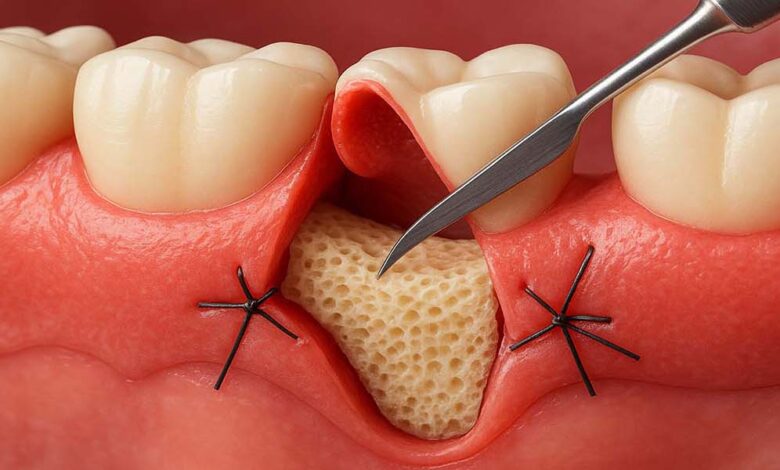

- جراحی فلپ: برداشتن بافت بیمار و پاکسازی عمیق.

- پیوند لثه: بازسازی بافت تحلیلرفته.

- پیوند استخوان: بازسازی استخوان تحلیلرفته برای حمایت از دندان یا ایمپلنت.